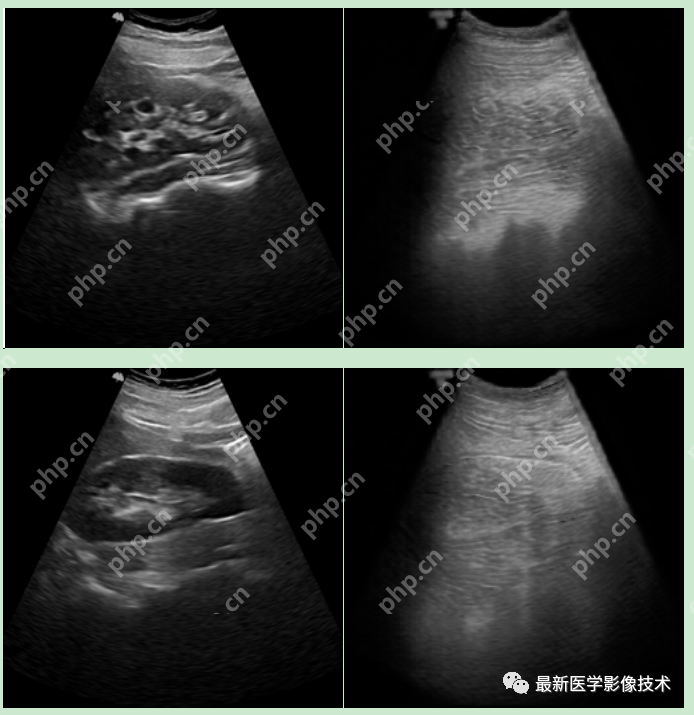

6、测试集部分生成结果

左图为低质量图像,右图为生成的高质量图像。